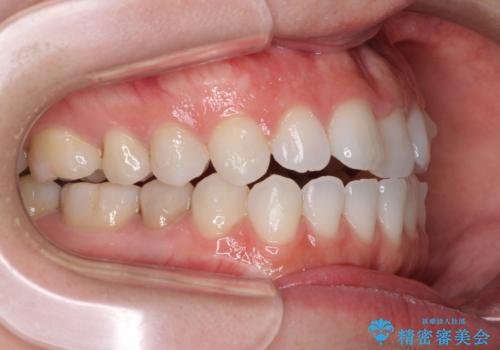

- 上下の前歯の反対咬合を気にして来院された患者様です。

インビザラインを用い、下顎はIPR(歯と歯の間を削る)と歯列全体を後方に移動させ、上顎は前歯を持ち上げることで、反対咬合を改善していくこととしました。

インビザラインによる反対咬合の改善は、上の歯が下の歯を乗り越えていく期間に咬み合わせが非常に不安定となり、治療が長期化することがあります。

こちらの患者様も、一時的に前歯でしか咬めない時期がありましたが、比較的早く咬み合わせが安定し、1年ほどで治療を終えることができました。